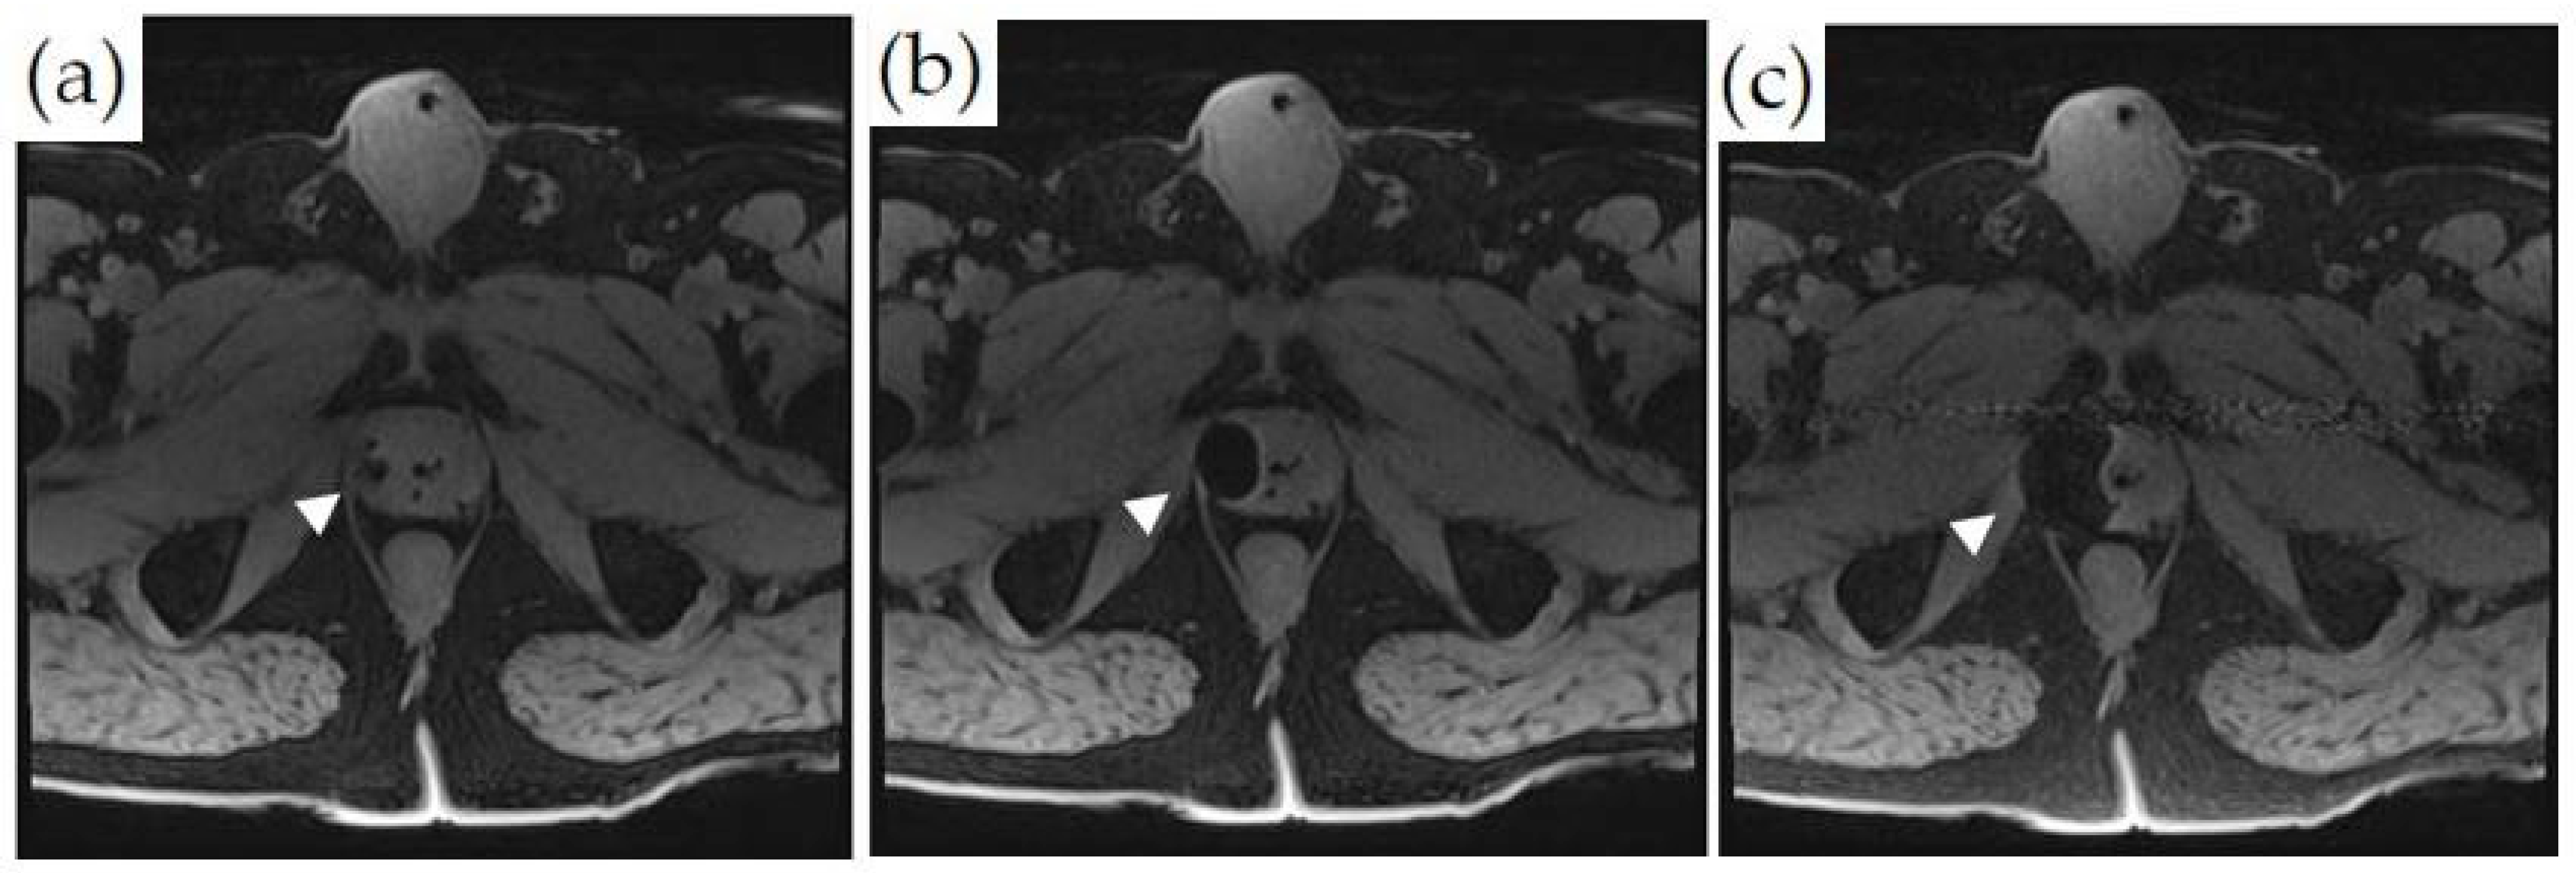

3.2. General MRI-Guided Thermal Therapy Monitoring

- PRF temperature mapping is highly sensitive to motion and tissue edge artifacts. Initially, a baseline comparison image is obtained, and all subsequent images are compared to it. As a result, any minor motion of the patient, bowel, or bladder can disrupt the baseline image alignment, causing phase registration artifacts. Reference-less temperature mapping has been proposed to alleviate this.